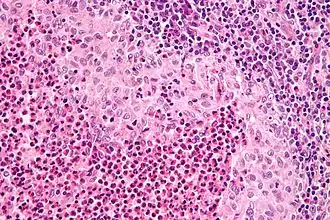

El diagnóstico se realiza por confirmación histológica a través de una biopsia tisular. La tinción de hematoxilina-eosina de la biopsia mostrará algunas características de las células de Langerhans como por ejemplo, gránulos plasmáticos rosados y margen celular distintivo. La presencia de gránulos de Birbeck en la microscopía electrónica y las características inmunohistoquímicas como por ejemplo la positividad para CD1, resultan pruebas más específicas. Algunos exámenes de laboratorio de rutina como el hemograma, perfil hepático, y otras pruebas sirven para orientar el diagnóstico (principalmente para descartar otras posibles causas). Los exámenes imagenológicos mostrarán lesiones osteolíticas y daño pulmonar. Esto último se puede evidenciar en la radiografía de tórax al mostrar lesiones micronodulares e infiltrados pulmonares en las zonas bajas y medias. La resonancia nuclear magnética o la tomografía axial computarizada puede mostrar infiltración a nivel de la silla turca. La medición del eje endocrino y la biopsia de la médula ósea también pueden resultar útiles para el diagnóstico.